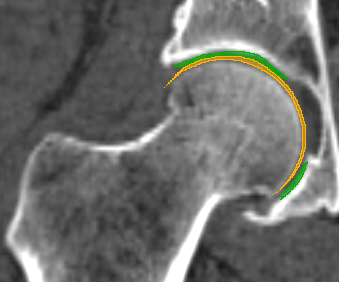

We have qualitatively verified that the articulating surfaces in all the ten HJs are detected correctly regardless of their anatomical variance using visual inspection of overlays as shown in Fig. 4. As desired, we observe a high degree of congruence between the opposing joint surfaces, meaning no gaps or overlaps in the cartilage-cartilage interface. Moreover, we observe a smooth transition towards the bone geometries as expected from the correct anatomy. The parameter values used to generate the cartilage from Fig. 5(a). The free parameters are the neighbourhood-size used to estimate the curvature of the bone (𝒩𝒩\mathcal{N}); the minimum and maximum curvature in the cartilage region (κmin,κmaxsubscript𝜅subscript𝜅\kappa_{\min},\kappa_{\max}; Eq. (2)); the distance parameter in mm𝑚𝑚mm (δ𝛿\delta; Eq. 1); and the number of times the outer boundary should be trimmed (Ntrimsubscript𝑁𝑡𝑟𝑖𝑚N_{trim}). Here, the curvature based parameters (𝒩,κmin,κmax)\mathcal{N},\kappa_{\min},\kappa_{\max}) are only used for the femur. See supplementary material for more visual comparisons.

Fig. 4 visualizes the von Mises stress pattern on the pelvic cartilage for one HJ. More are shown in the supplementary material. We have verified that no spurious stress peaks appear and that stress values change gradually and smoothly across the cartilage. Further, the high-stress areas are located in the up-direction, as we expect from the applied displacements. The stress values and patterns are not to be confused with those from a real stance. They only serve as a verification test of simulation properties. For such a simulation, we require ligaments and muscles to stabilize the girdle and a correction from sublime pose bias.

Refer to caption

(a) Von Mises stress.

(b) CT scan overlay.

Figure 4: The von Mises stress patterns ((a)) and the generated cartilage imposed on the CT scan from which the bone was extracted ((b)). Notice the high level of congruence in the cartilage-bone interfaces and cartilage-cartilage interface.